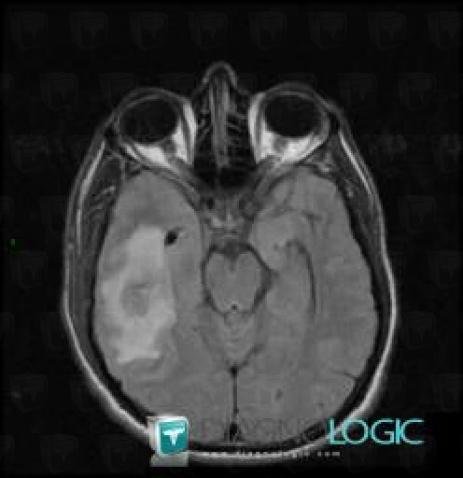

Abscess, Cerebral hemispheres, MRI

Here is the specific information in the key image above:

- Diagnosis Abscess, Location(s) Cerebral hemispheres, with gamuts Temporal lobe T2WI or FLAIR hyperintense lesion, Intracerebral T2W or FLAIR hyperintense lesion